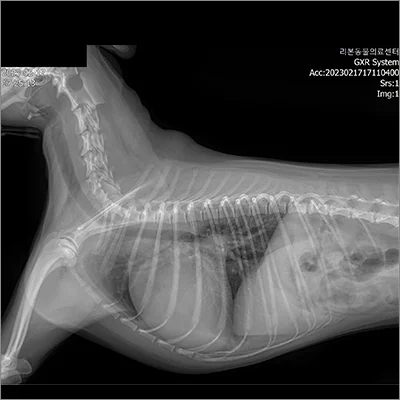

PDA 전

PDA 후